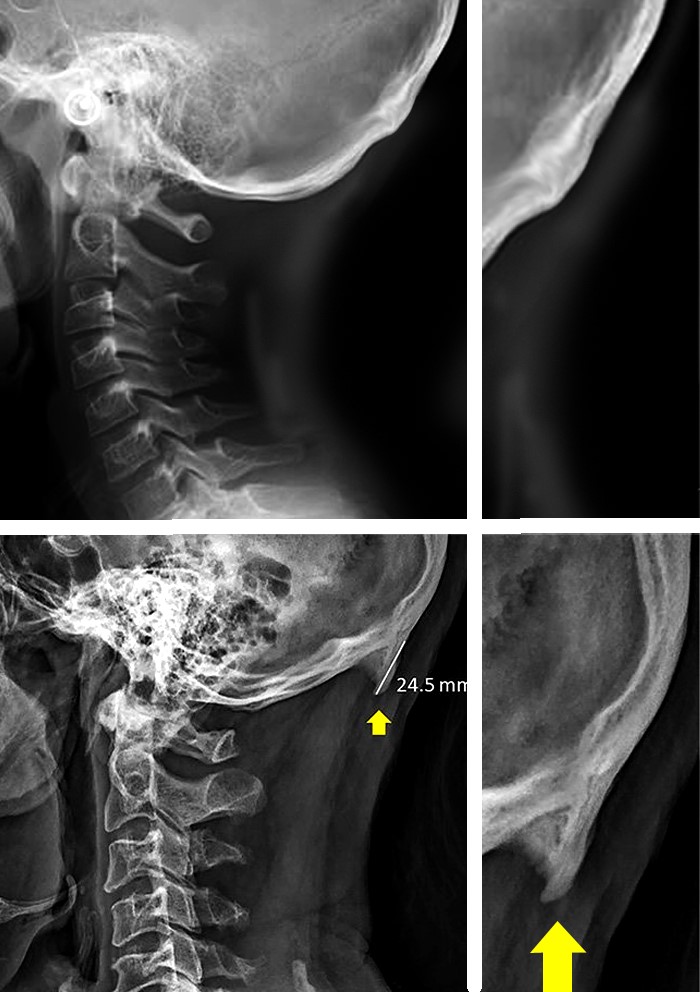

Neki od tih 'roščića' su dugi manje od par milimetara i jedva su primjetni, no neki mjere i preko 3 cm duljine. Opisane rodolike izrasline su locirane na vrlo određenom mjestu na lubanji: straga, iznad mjesta pripoja glave i vrata, nalazi se zatiljna (okcipitalna) kost, a na njezinoj sredini je prirodna koštana kvržica nazvana vanjska zatiljna izbočina (latinski: protuberantia occipitalis externa, POE), koja je normalno hvatište ligamenata i tetiva vratnih mišića.

Uspoređujući s istraživanjima (ne)pravilnog držanja glave i vrata u ranijim desetljećima, utvrdili su da je u ovoj studiji izmjerena prosječna hiperfleksija (savijanje glave prema naprijed) od 26 mm, što je statistički znatno veća vrijednost od one izmjerene 1996. godine, kada takvih ručnih napravica još nije bilo.